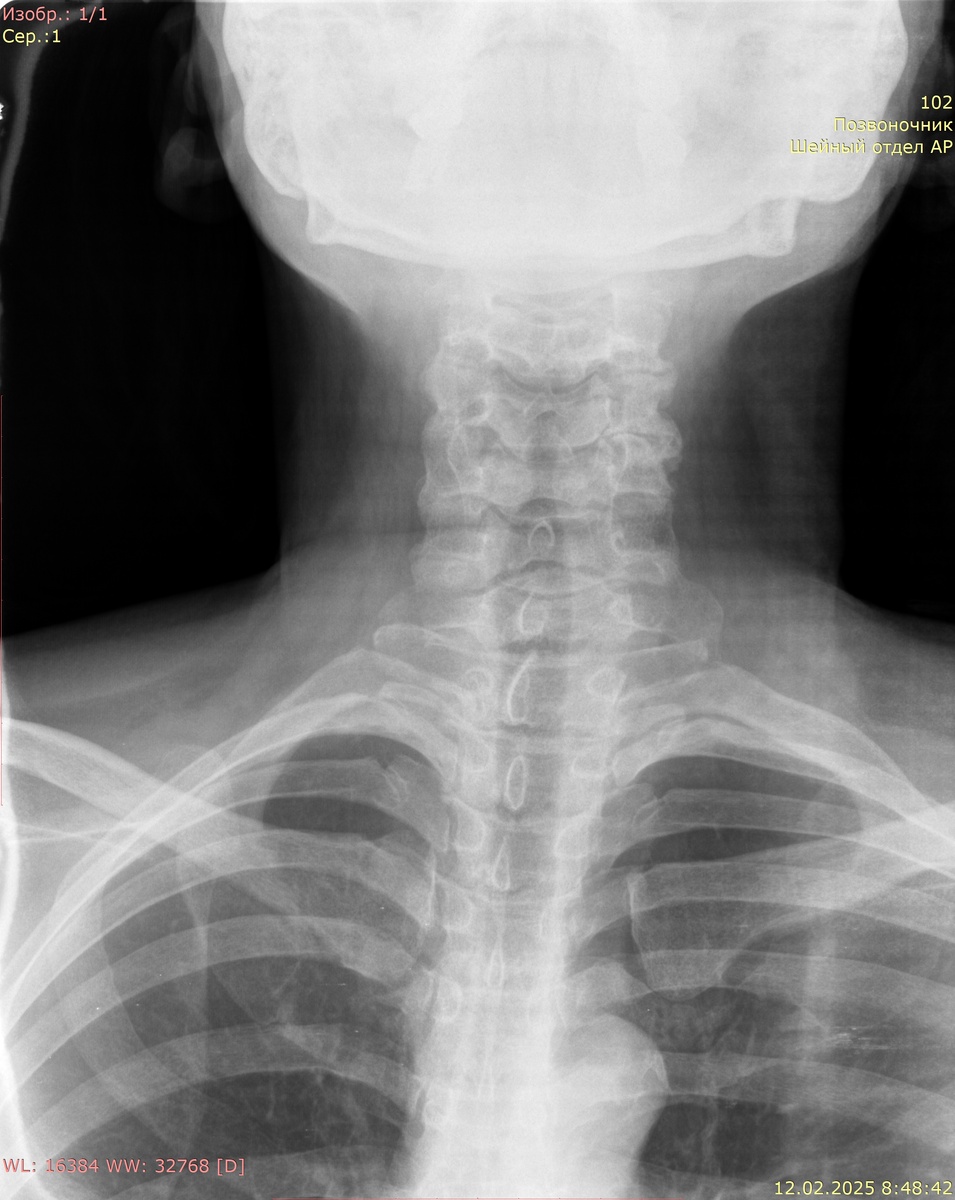

Рентгенография шейного отдела позвоночника в двух проекциях:

Аномалий развития не выявлено. Шейный лордоз сглажен. Ось позвоночника не нарушена. Соотношение позвонков правильное. Высота и структура тел позвонков не изменена. Субхондральный склероз замыкательных пластинок тел позвонков, неравномерное снижение высоты межпозвонковых дисков в задних отделах С3-С7. Костно-травматических и костно-деструктивных изменений не выявлено.